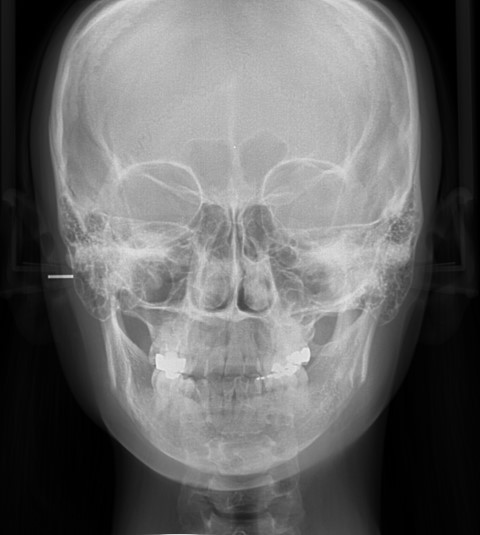

수술 후

비대칭이 상당히 완화되었고 부기가 소실된 후 육안으로는 비대칭증상을 전혀 발견할 수 없을 만큼 증상이 호전되었습니다. 긴곡선절제술을 이용한 비대칭교정은 절제범위를 다르게 하는 것이 포인트로 앞턱까지 잘라내는 길이 및 넓이모두 달리해야 하기 때문에 숙련된 노하우가 필요합니다.